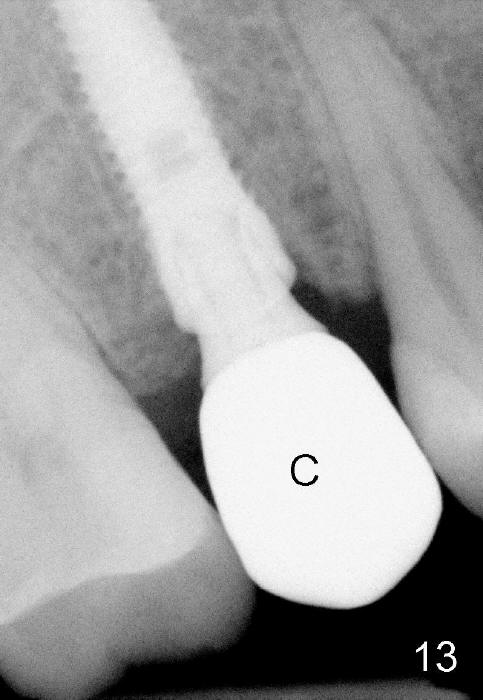

Due to insurance termination, restoration has to be done 2 months post implantation. Both the soft (Fig.10 *) and hard (Fig.11) tissues heal normally. A cemented abutment is placed (Fig.12 A). Fig.13 is taken 5 months post cementation. There is no bone resorption.